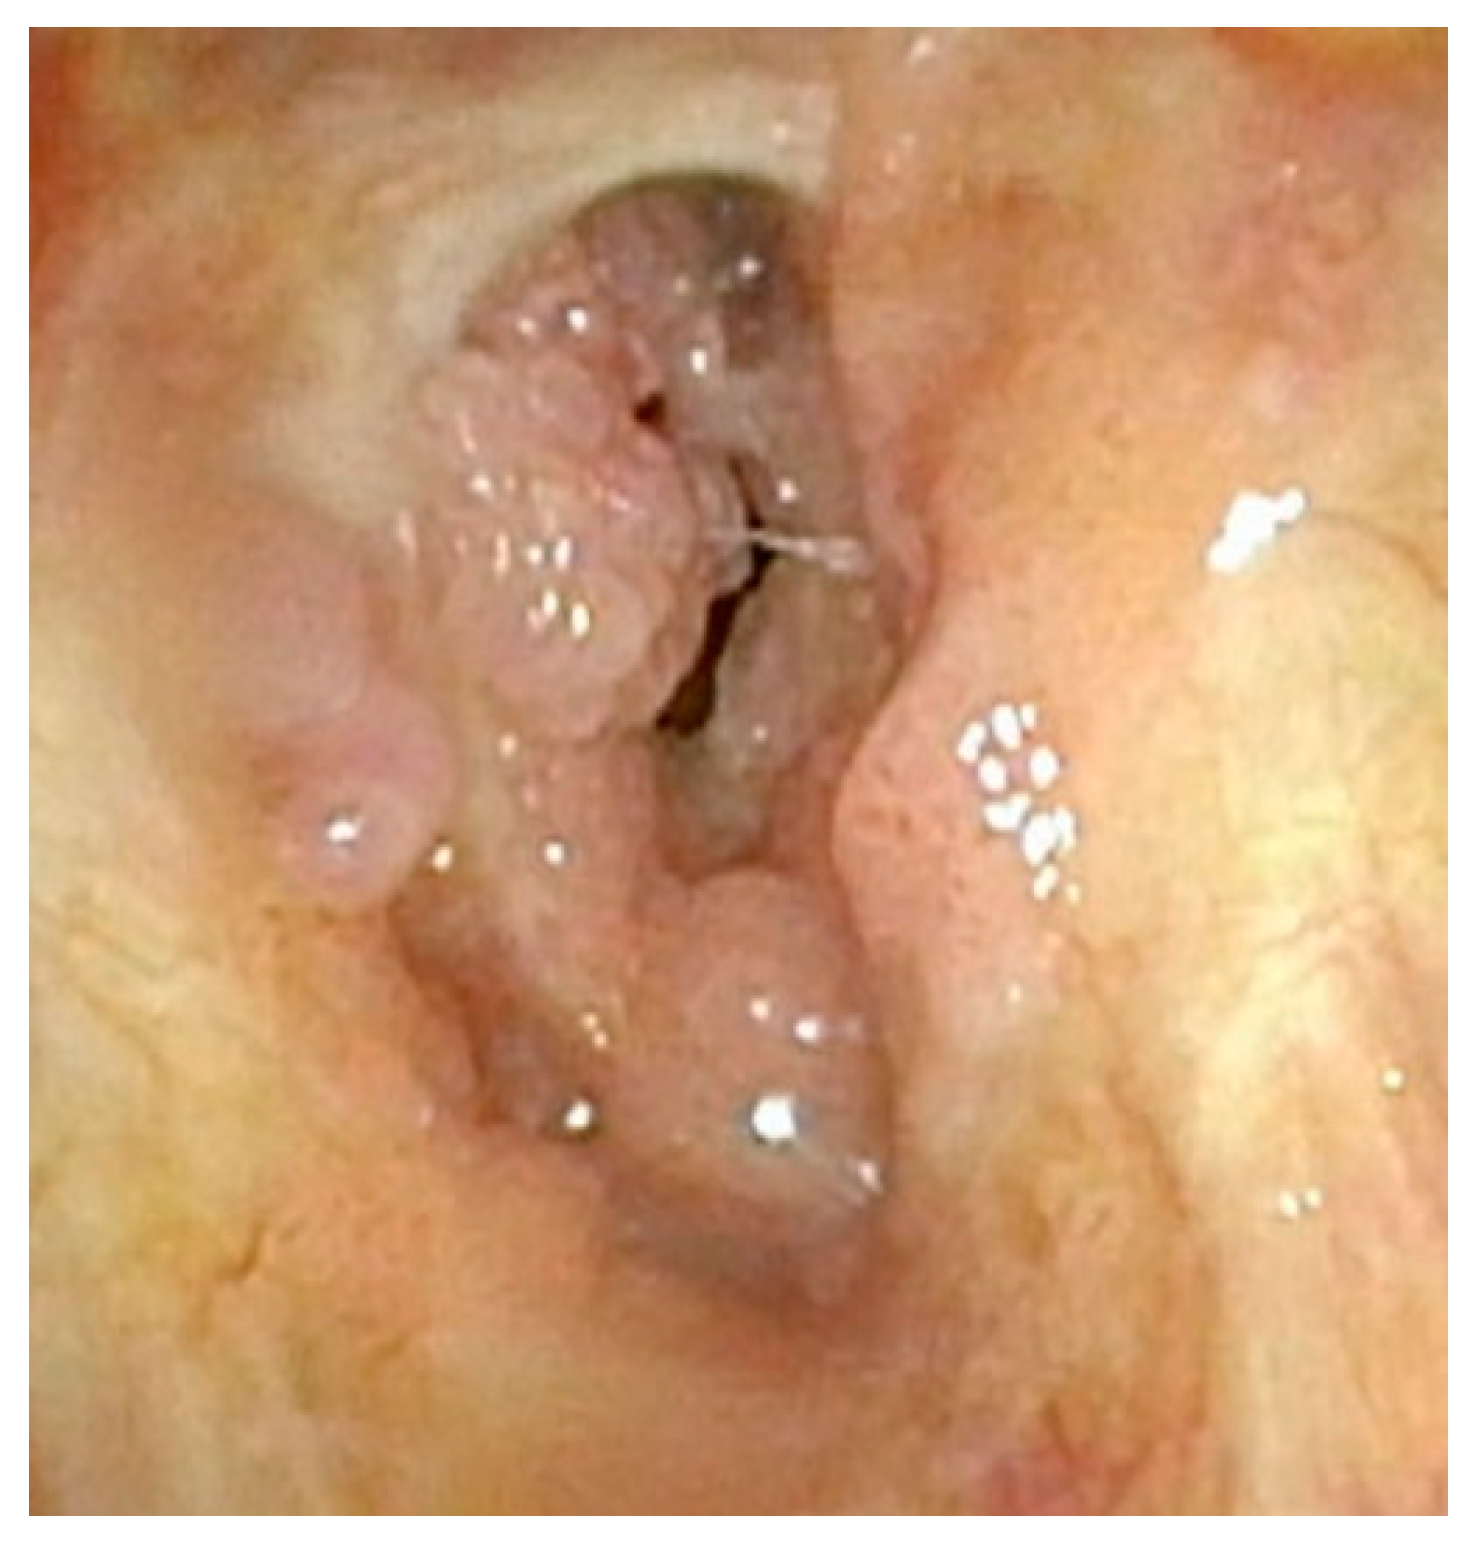

Although less common, care must also be taken not to disrupt the mucosa along the entirety of the posterior commissure. Should this occur, a patient is at great risk of developing posterior glottic stenosis (Figure 4). This should also be treated similarly to the anterior glottic web with midline lysis of the scar and injection of steroids, and dilation should always be performed in these cases (Figure 5). The combination of anterior or posterior glottic stenosis in the setting of a patient with papillomas can lead to significant airway obstruction and should be avoided in all cases with careful surgical attention (Figure 6).

Figure 4.

Significant papillomatous growths throughout supraglottis and severe posterior glottic web.